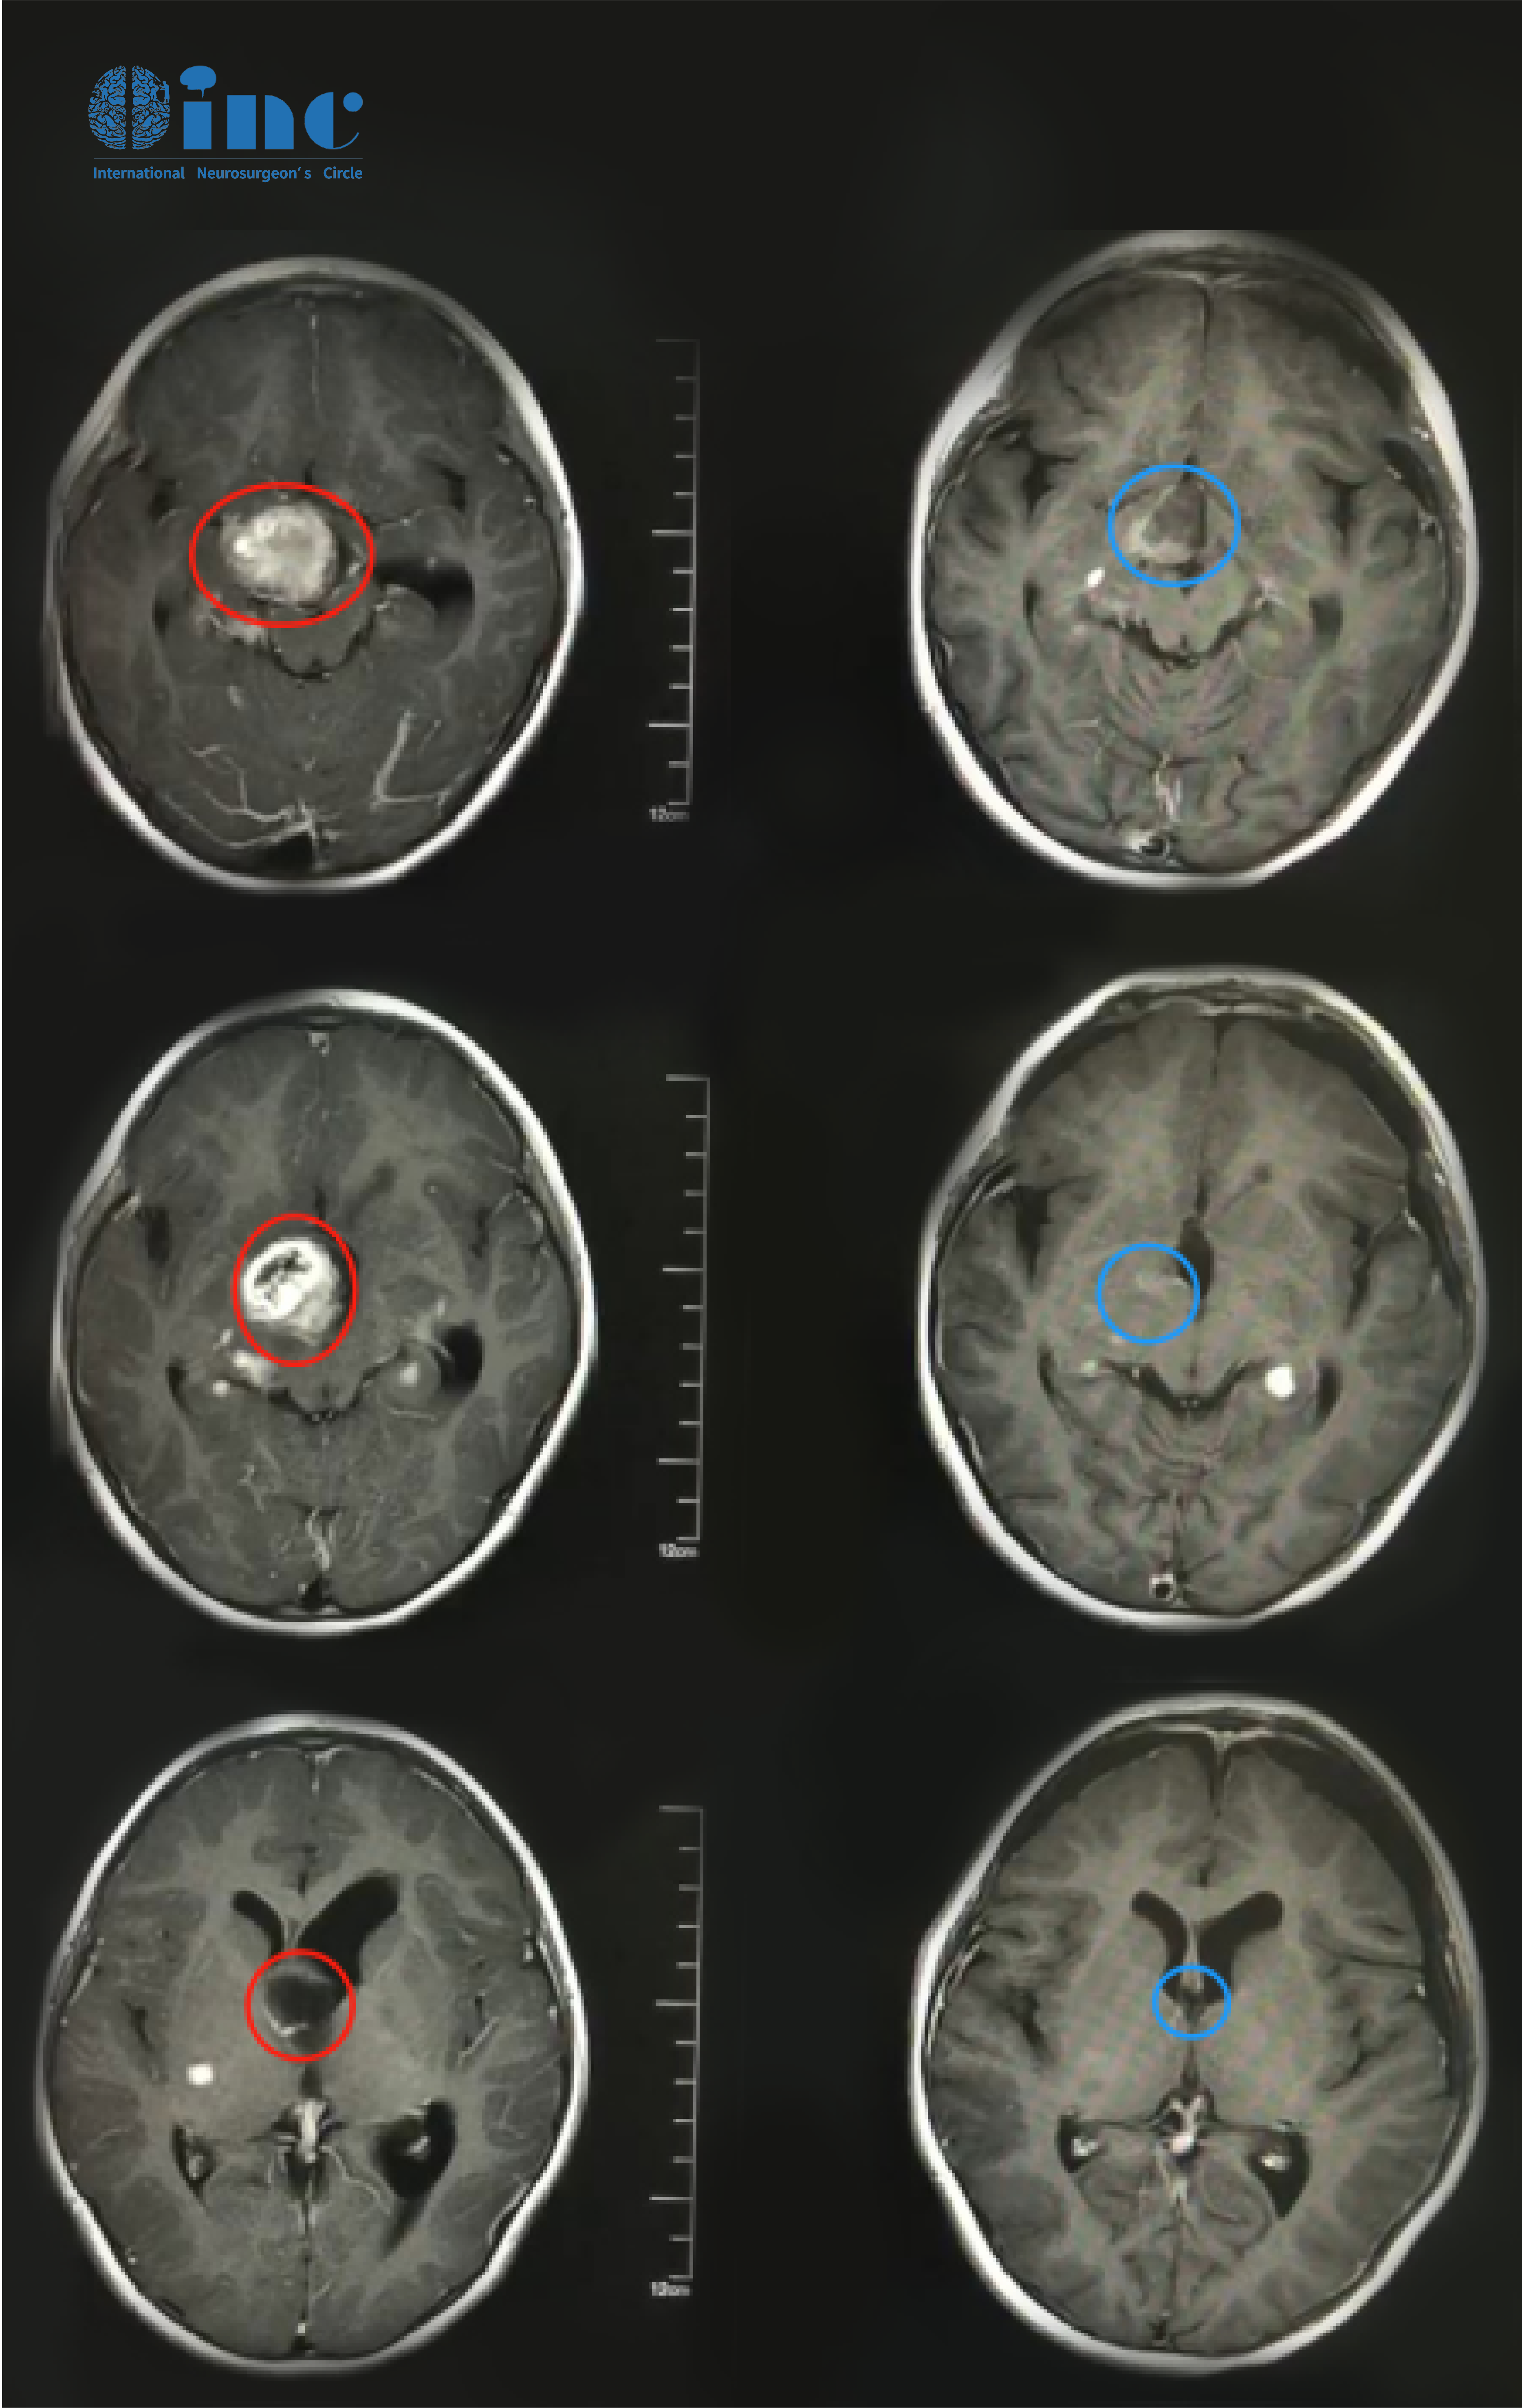

康康的術前MR影像

康康的術前術后MR影像對比